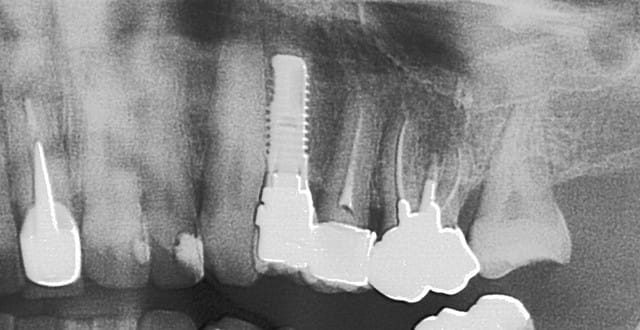

http://www.implantdirect.com/us/pop-out/ScrewPlant_Tour_HiQ.htm

c'est pas une connexion conique...

première radio à la pose en 2007

deuxième en 2013....

enfin tout çà pour voir qu'en 6 ans çà n'a quasi pas bougé...

un autre...contrôle 2013...implant posé en...2004...un de mes premiers

serf EVLN...connexion plus à plat, tu peux pas....